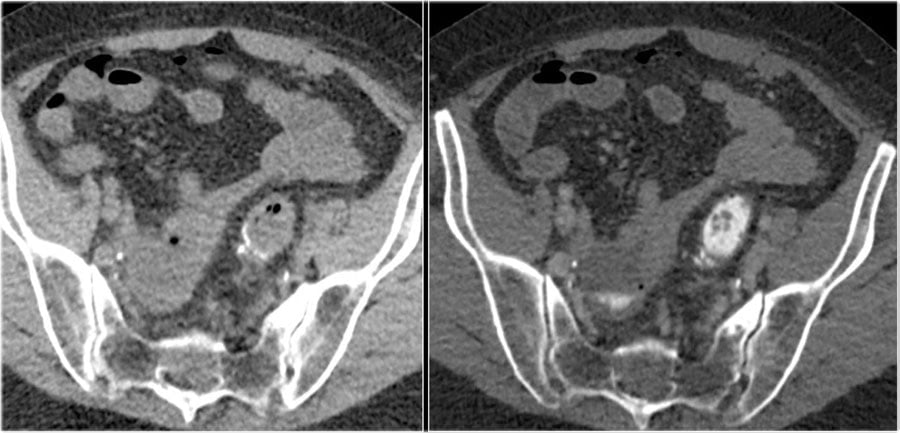

Nefrogenic phase

100 sec p.i. or 80 sec after bolustracking

Enhancement of:

– All renal parenchyma including medulla

Detection of:

– Renal cell carcinoma (arrow)

Thì thận

100 giây sau tiêm thuốc hay 80 giây sau bolus tracking.

Tăng quang:

– Toàn bộ nhu mô thận, bao gồm cả tủy thận.

Giúp phát hiện:

– Ung thư tế bào thận (mũi tên)